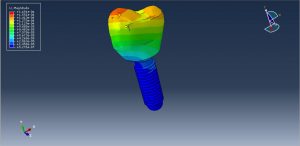

During the analysis, the force causes the stress in the assembled parts and the critical zone can be extracted from the model. You can see some figures for the results below